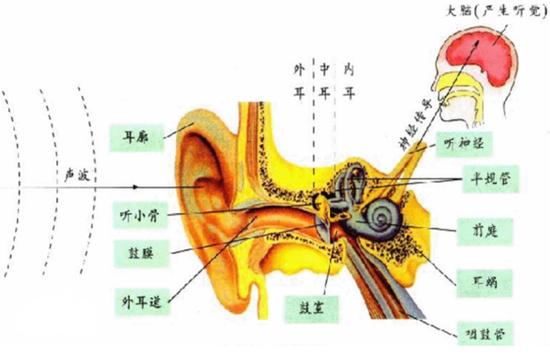

此外,为了进一步研究阳光辐射对脑神经的影响,研究者们测试了受试者的脑干听觉诱发电位。什么是脑干听觉诱发电位?我们先来解释下什么是听觉通路。如下图,我们耳朵的外耳、中耳感受到的声波振动传递到内耳,在内耳耳蜗转变成生物电信号然后再通过听神经一直传递到大脑皮层,人们才可以听到声音。

听觉传到通路(图片来源:百度百科)

脑干听觉诱发电位是一项反应脑干受损情况的客观指标。仪器会记录声音发出后18毫秒以内和听相关的电位反应,继而反映耳蜗至脑干相关结构的功能状况。凡是累及听觉通路的任何病变或损伤都会影响这一指标。

听觉脑干诱发电位能客观敏感地反映中枢神经系统的功能,往往脑干轻微受损而临床无症状和体征时,它就已经发生了改变。本次研究通过测量这一指标发现,长时间施加模拟阳光辐射时(大约2小时,直到核心温度升高1度),受试人员的脑干听觉诱发电位将发生变化,而在急性(15分钟)阳光辐射暴露下,没有表现出受到影响的痕迹。